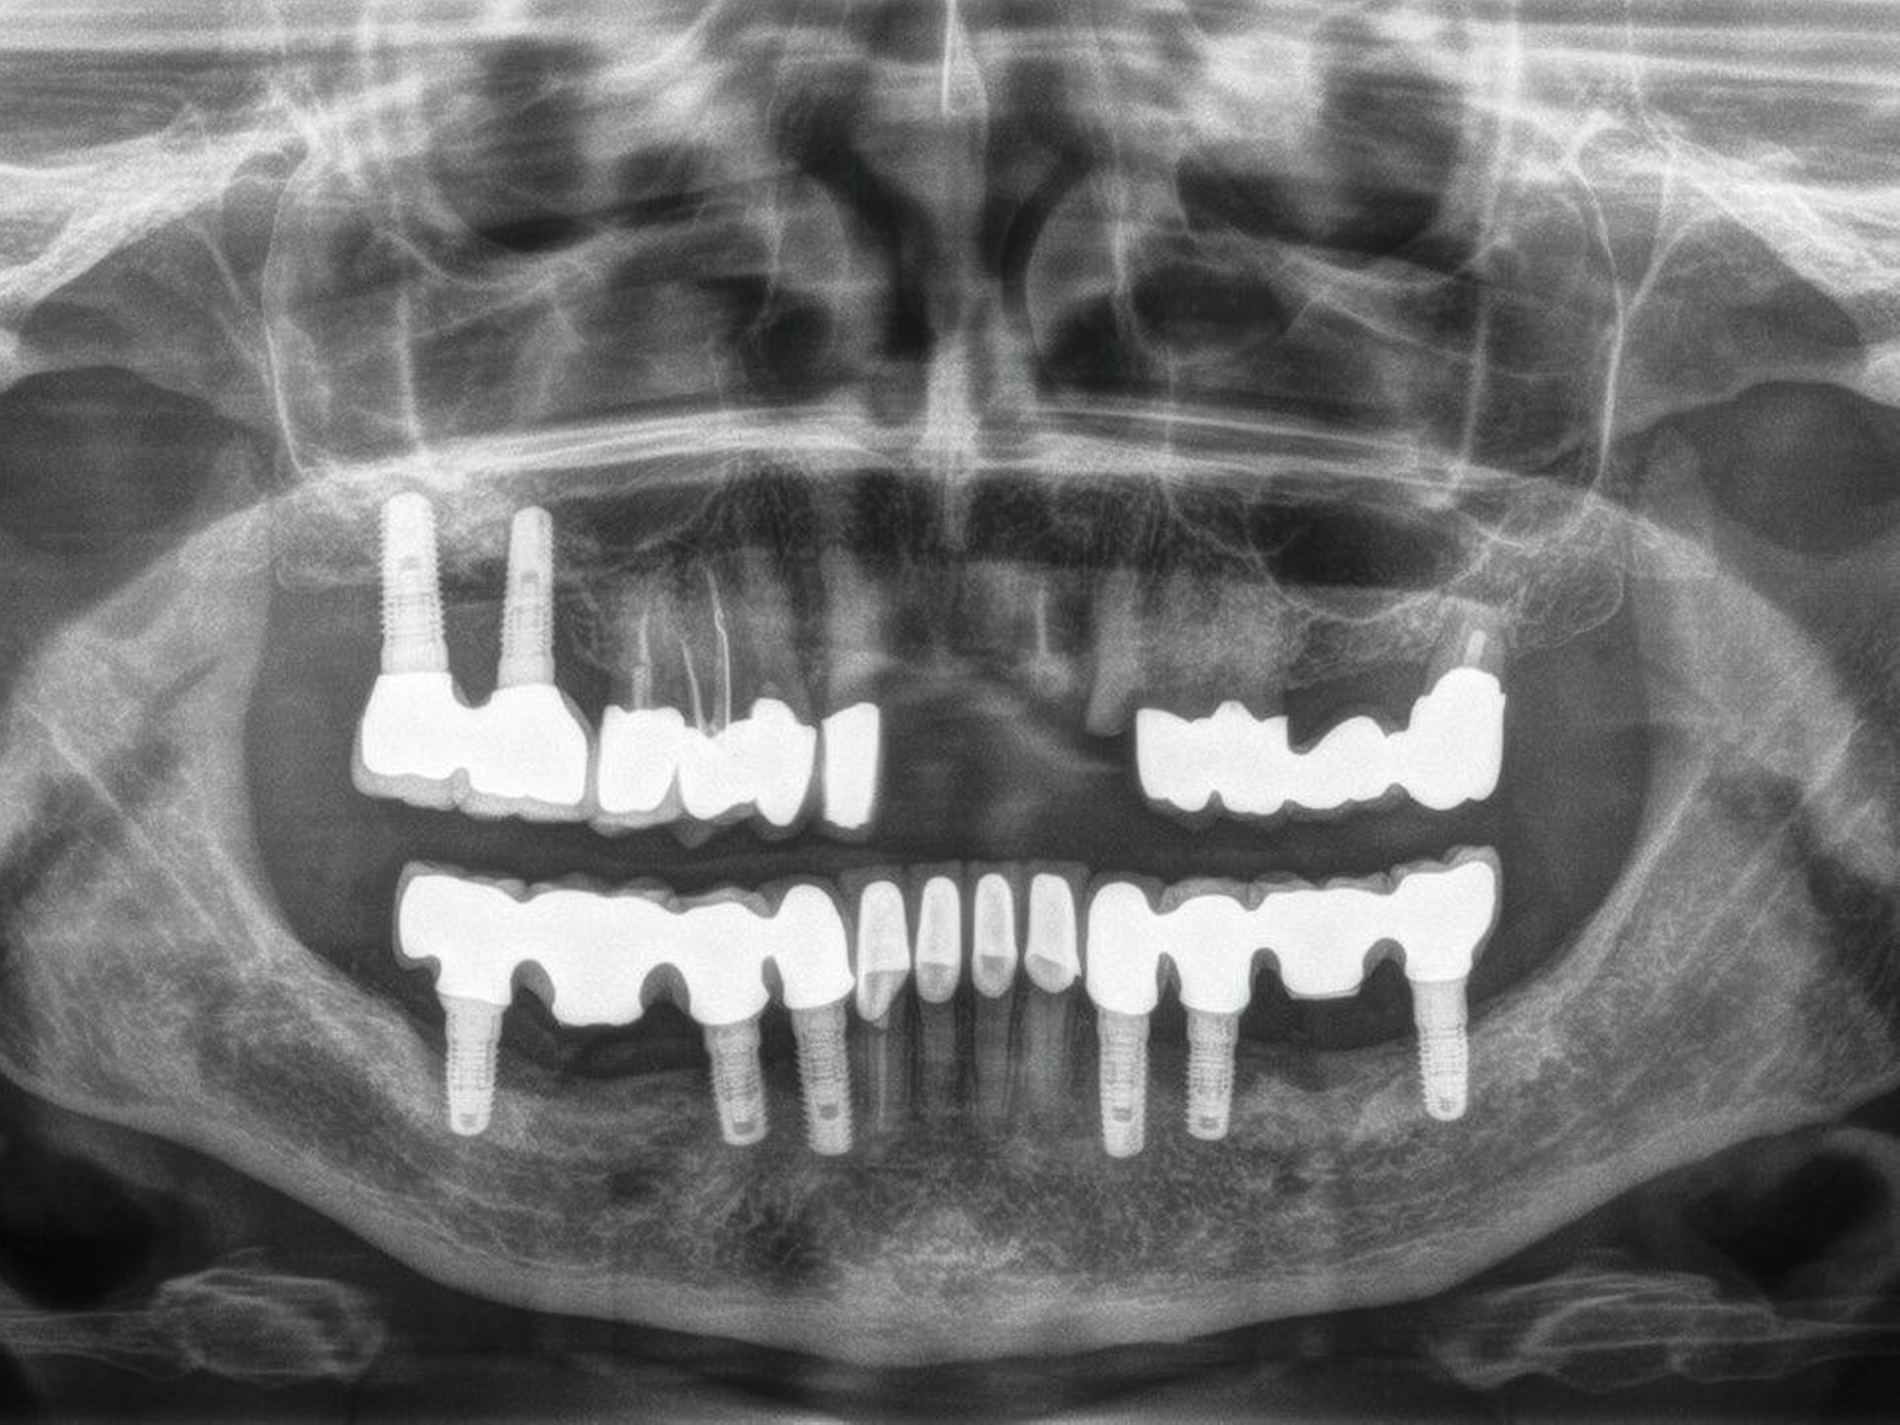

Abbildung 4 zeigt eine Milchzahn-Transplantation im frühen Wechselgebiss bei einem achtjährigen Mädchen bei nahezu vollständiger Ersatzresorption des Zahnes 11 nach Avulsion und Replantation. Trotz des sehr guten Zustands des Milchzahntransplants im Alter von zwölf Jahren entschied man sich in Rücksprache mit den Kollegen der Kieferorthopädie für die Prämolaren-Transplantation als eine zuverlässige Versorgung mit Überlebensraten von im Mittel 96,7 Prozent nach 8,75 Jahren [Akhlef et al., 2017]. Die Planung der Prämolaren-Transplantation sollte dabei immer in enger Absprache mit der Kieferorthopädie erfolgen, um zu klären, ob die Entnahme eines Prämolaren vertretbar und welche Entnahmestelle die geeignetste ist.

Zahnimplantate und dentales Trauma

Bei einer Avulsionsverletzung ist bei gesunden Zähnen der Replantation der Vorzug zu geben. Auch Zähne mit schlechter Prognose aufgrund langer extraoraler Trockenlagerungszeit sollen nach der aktuellen Leitlinie replantiert werden, weil sie mit großer Wahrscheinlichkeit ankylotisch einheilen und daher die Wurzel langsam durch Knochen ersetzt wird.

Dieser sekundär gebildete Knochen ist ein gutes Lager für Zahnimplantate oder im Wachstumsalter für ein autologes Zahntransplantat. In der Wachstumsphase sind Zahnimplantate möglichst zu vermeiden, weil aufgrund der ankylotischen Einheilung von Zahnimplantaten eine Infraposition der implantatgetragenen Restauration droht. Dies gilt insbesondere, wenn bereits vor dem pubertären Wachstumsschub implantiert wird. Zur Lückenversorgung im Wachstumsalter steht neben Provisorien die Adhäsivbrücke, der kieferorthopädische Lückenschluss oder die autologe Zahntransplantation zur Verfügung (Tabelle 2).

Zur Vorbereitung einer Implantatversorgung zu einem späteren Zeitpunkt sind im Wachstumsalter Maßnahmen förderlich, die die replantierten Zahnwurzeln und den Alveolarfortsatz über den pubertären Wachstumsschub konservierend erhalten, beispielsweise die oben erwähnte Dekoronation mit provisorischer Erhaltung der Wurzeln oder die chirurgische Anluxation ankylosierter Zähne. Im Erwachsenenalter verläuft die Ersatzresorption bei Ankylose deutlich langsamer als im Kindesalter, so dass replantierte Zähne auch nach Ankylose durchaus als eine längerfristige Versorgung angesehen werden können.

Die Versorgung einer Lücke mit Zahnimplantaten nach einem dentalen Trauma wird in der Regel nach Abschluss des pubertären Wachstumsschubes erwogen oder besser noch ins frühe Erwachsenenalter verlegt. Wenn zu diesem Zeitpunkt keine Sofortimplantation zusammen mit der Zahnwurzelextraktion erfolgt, sollte die Möglichkeit der Ridge preservation geprüft werden. Wenn eine Versorgung mit Zahnimplantaten erfolgt, dann nicht in der Akutphase des Traumas, sondern nach Abheilung der Weichteilwunden und der direkten allgemeinen Traumafolgen (Abbildung 5).